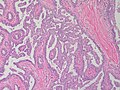

Nipple adenoma. H&E stain.

LM proliferation of epithelial and myoepithelial elements that extends into the breast stroma; not encapsulated; lacks true fibrovascular cores, +/-focal necrosis

• Arborising papillomatous epithelial proliferation within duct

• (Papillae have fibrovascular cores) at least as far as I can see but not according to Stanford.

• Florid epithelial hyperplasia can be seen

• Lacks true fibrovascular cores.[5]

• Focal necrosis may be present.[6]